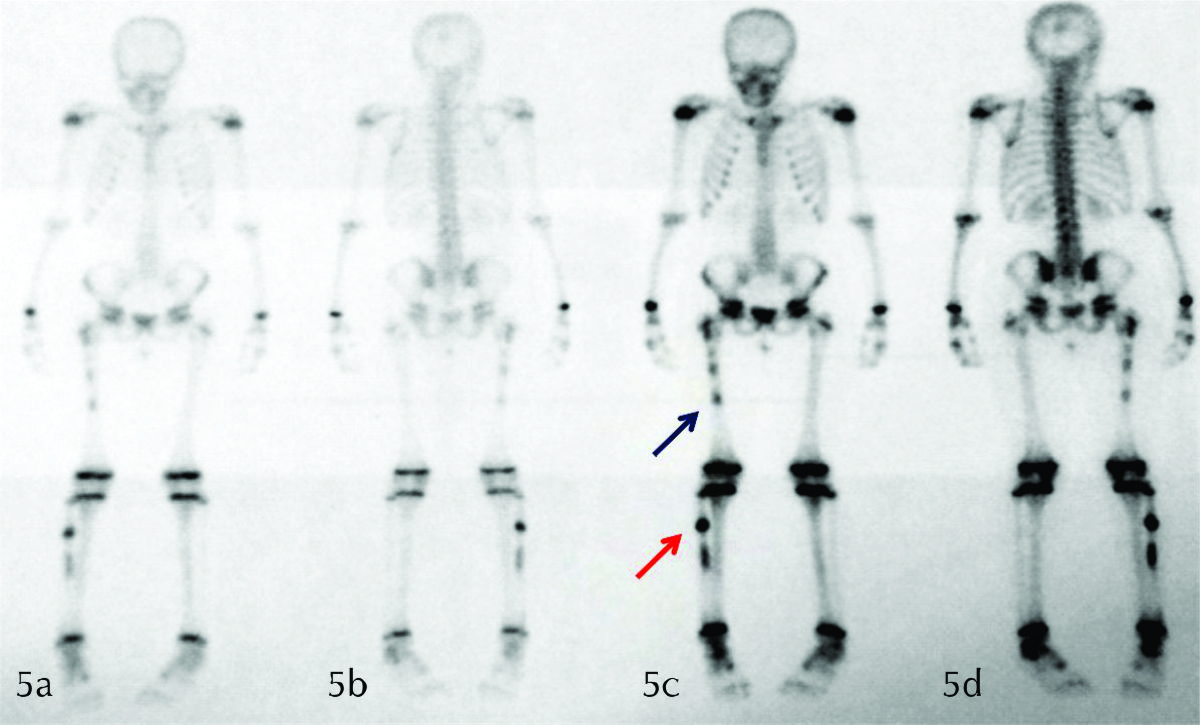

Figura 5

SPECT planar en proyección anterior (a-c) y posterior (b-d), en una fase temprana (a-b) y otra tardía (c-d). Se observa intensa captación del radio-trazador 99Tc-MDP a nivel del fémur proximal derecho (flecha azul), tanto diafisario como metafiso diafisario, y a nivel del peroné homolateral (flecha roja).